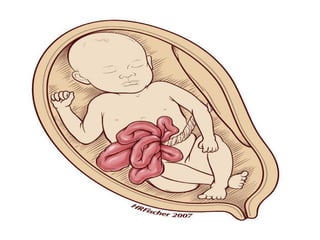

• An opening in the abdominal wall through

which the internal organs push outside of

the baby's body

• Usually on the right side of the umbilical

cord

• The child's intestines can be easily seen

What is gastroschisis? •An opening in the abdominal wall through which the internal organs push outside of the baby's body • Usually on the right side of the umbilical cord • The child's intestines can be easily seen